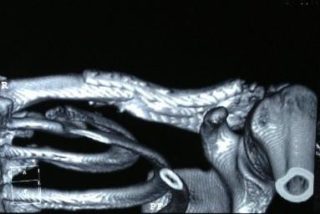

Самое четкое изображение можно получить при КТ плечевого сустава

Чтобы понять, почему возникла болезненность, нужно обратиться к врачу-ортопеду. Он назначит подходящие анализы и диагностику, которая обычно состоит из следующих процедур:

- рентген плечевого сустава и ключицы – показывает состояние костей, помогает выявить травмы, остеомиелит и артриты;

- КТ и МРТ – тонный и информативный способ диагностики, показывающий состояние не только костей, но и структур рядом с ними;

- артроскопия – устаревший эндоскопический метод, который используется очень редко, но дает точные результаты путем исследования внутренней части сустава;

- УЗИ – доступная процедура, которая показывает состояние суставной сумки.

Иногда пациентам требуется пункция суставной полости, используемая преимущественно при инфекционных поражениях. С помощью пункции удается установить тип возбудителя.